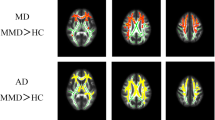

As compared to the group of healthy controls, the patient group with vascular MCI and SVD showed extensive areas of increased MD and RD and of decreased FA involving cerebral WM, corpus callosum, thalami, brainstem, superior and middle cerebellar peduncles and cerebellum (Supplementary Figs. 1-3). Areas of increased AD were also present in the cerebral WM, corpus callosum and thalami (Supplementary Fig. 4). No areas of significantly decreased MD or RD, of increased FA or decreased AD were observed.

Within-group regression TBSS analysis of the midline structures in patients with vascular MCI and SVD. TBSS reveals that the values of DTI-derived indexes are correlated with individual MoCA scores. In particular, FA (in red) values are significantly (p value <0.05 corrected, threshold-free cluster enhancement) correlated (positive correlation) with MoCA score, whereas MD (in yellow) and RD (in green) values are significantly correlated (negative correlation) with MoCA score. In the MD and RD maps, note the spot in the upper midbrain corresponding to the decussation of the superior cerebellar peduncles. See text for abbreviations